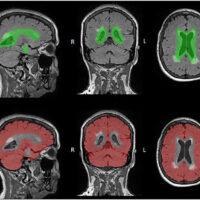

MRI Study Examines Functionality of Key Brain Structures

Exploring the functional connectivity between the striatum and cerebral cortex.